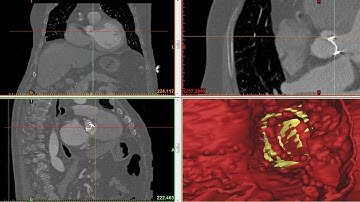

3D unsteady FSI computation of the hemodynamics through a model of aortic valve